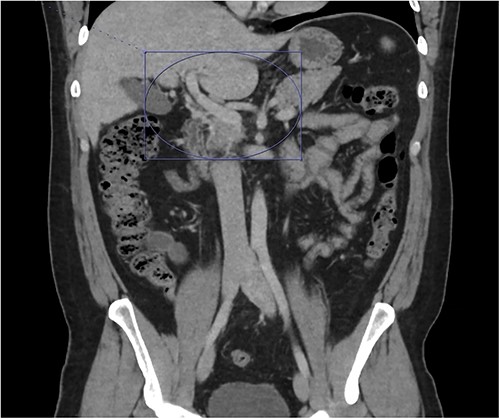

Thrombosis can be seen extending into the mesenteric venous system as well as the intrahepatic portal veins; associated mesenteritis and abdominal ascites (not well visualized) are also seen.

Patient was admitted to the surgical service and started on broad-spectrum IV antibiotics (piperacillin–tazobactam) and was made nil per os. He was resuscitated intravenously with 2 l of crystalloid. Given the thrombosis of his PV and SMV, the patient was initiated on systemic anticoagulation with IV heparin which achieved therapeutic dosing within 24 hours. Over the course of the next few days, his abdominal pain and tachycardia improved. Interval CT abdomen/pelvis scan 5 days from presentation demonstrated progression of the thrombus to involve lobar, segmental, and subsegmental portal venous branches as well as the splenic vein distal to the portosplenic confluence (Fig. 2).